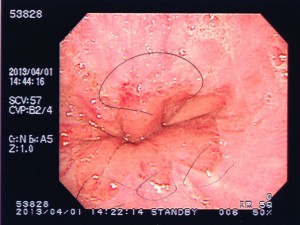

初の胃カメラですが、検査中モニターで視認できます。医師の説明を聞きながら進めますが、質問したくても口はふさがれています。「綺麗なサクラ色ですよ~」などと褒められて複雑な心境です。

さて、肝心の結果ですが、胃潰瘍の中レベルが検出されました。より詳細に言うならば「逆流性胃腸炎」から発症しているようです。特に重度ではないので、お薬で完治するようです。問題なのは生活習慣の改善です。食事の時間が超不規則、寝る前に食事をとる、睡眠不足、ストレス、過度の飲酒、これらはご法度だそうです。なかなか難しい課題ですが、健康管理もプロの仕事、「しっかり守ります、先生」と言って病院を後にしました。

毎度、被害者の皆様から医療写真の提供、協力をいただいておりますので、たまには自らも写真公開します。

← 〇の部分が赤く炎症を起こしています。